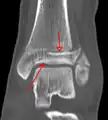

Une fracture triplane de la cheville vue sur une radiographie standard

Une fracture triplane de la cheville vue par TDM